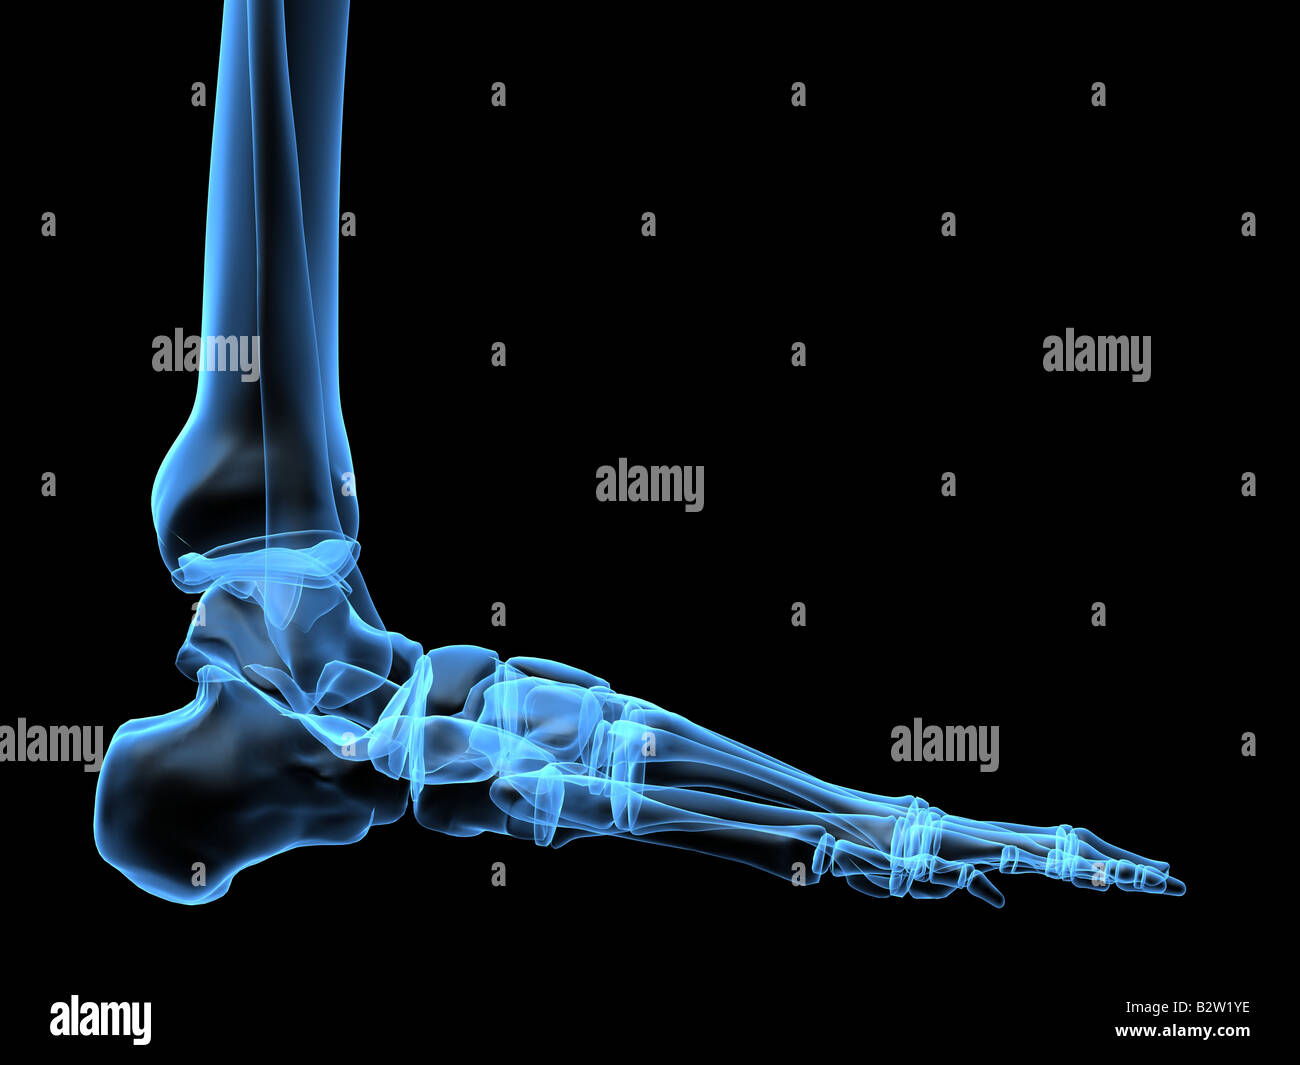

RF2R3WKY1–Illustration médicale des principales parties des os du pied en vue latérale, avec annotations.